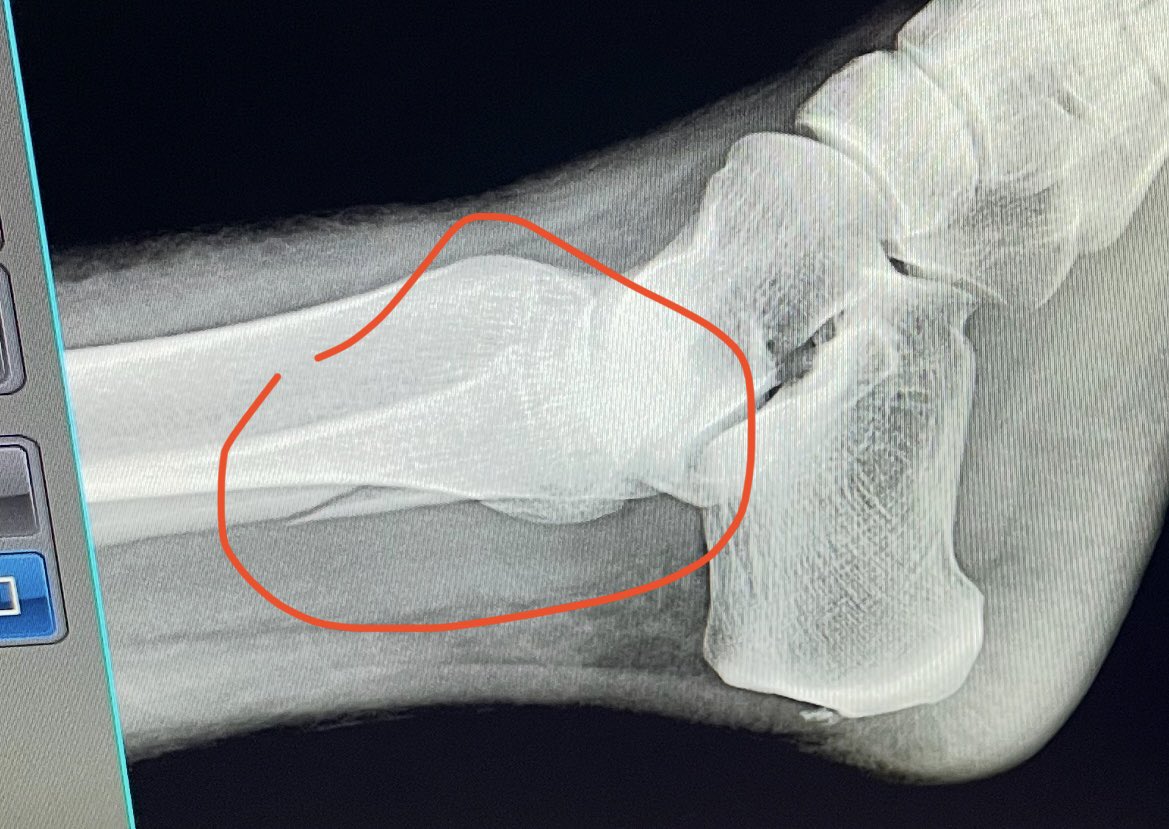

lght.ly/f218o20 Dr Moez Zeiton, DNF Faculty and orthopaedic and trauma surgeon, talks on a podcast with the British Hip Society, and references his work with our Foundation. We are lucky to have you, Moez! #traumasurgeon #surgicaltraining #warsurgery